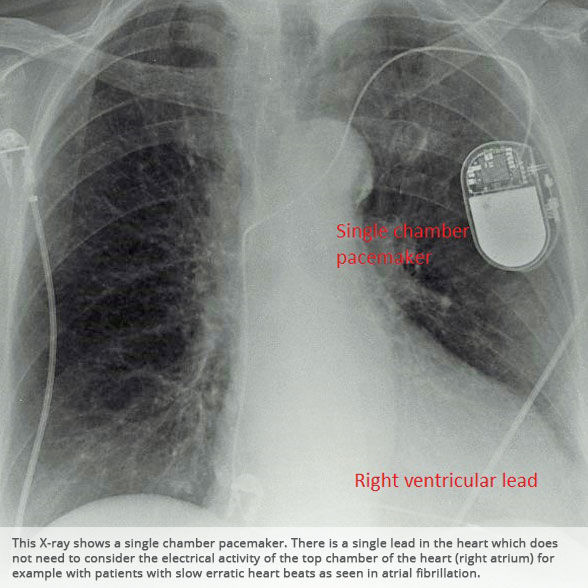

From www.pedicardiology.net

Pedi cardiology How to identify pacemaker? Dental X Rays And Pacemaker the dental literature also included articles regarding electromagnetic interferences to pacemakers, due to dental devices such. some dentists, like myself, have pacemakers and follow this information for both ourselves and our patients. this review article will discuss the various types and indications for. Learn about these procedures below and be sure to tell your dentist. electromagnetic. Dental X Rays And Pacemaker.